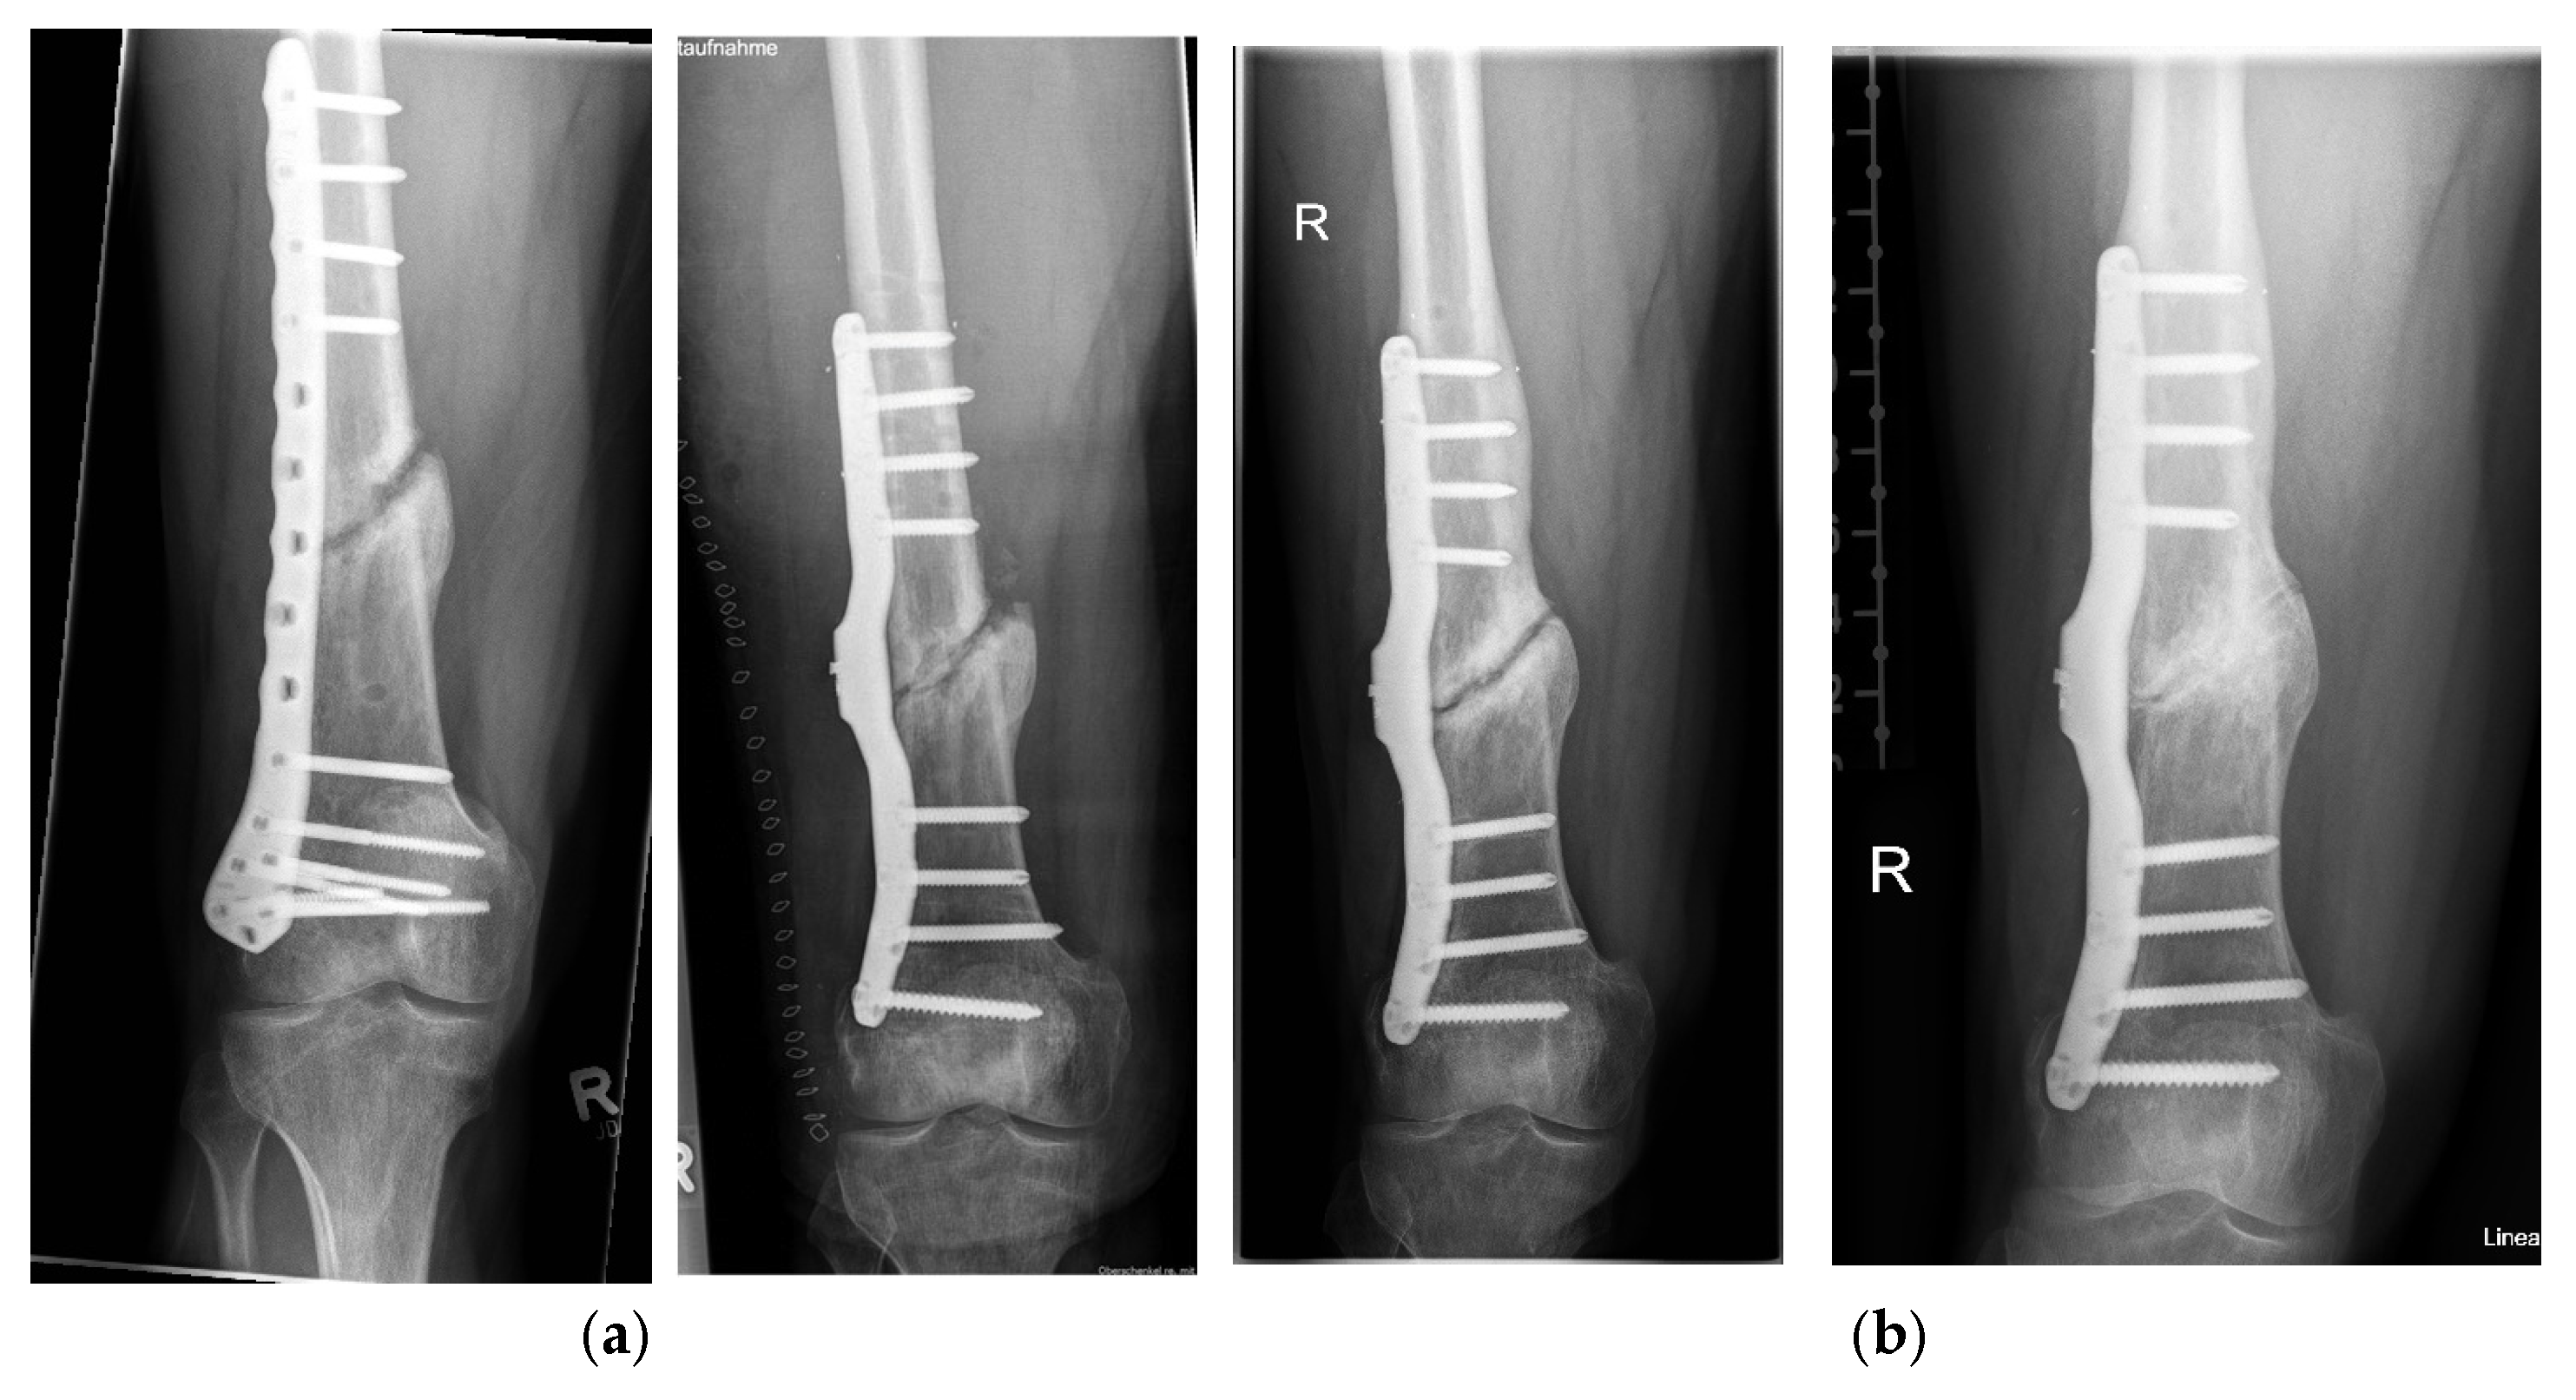

- Seide, K.; Aljudaibi, M.; Weinrich, N.; Kowald, B.; Jürgens, C.; Müller, J.; Faschingbauer, M. Telemetric assessment of bone healing with an instrumented internal fixator. J. Bone Jt. Trauma Surg. 2012, 94-B, 398–404. [Google Scholar] [CrossRef]

- Kowald, B.; Seide, K.; Auerswald, M.; Faschingbauer, M. Slow-healing non-unions. Measurement of mechanical stability with the instrumented implant. 3 case reports. Trauma Berufskrankh. 2019, 21, 181–192. [Google Scholar] [CrossRef]

- Faschingbauer, M.; Seide, K.; Aljudaibi, M.; Kowald, B.; Münch, M.; Weinrich, N.; Jürgens, C.; Moss, C.; Kirchner, R. Intelligent implants for monitoring bone healing. Trauma Occup. Dis. 2013, 15, 240–248. [Google Scholar]

- Kienast, B.; Kowald, B.; Seide, K.; Aljudaibi, M.; Muench, M.; Faschingbauer, M.; Juergens, C.; Gille, J. An electronically instrumented internal fixator for the assessment of bone healing. Bone Jt. Res. 2016, 5, 191–197. [Google Scholar] [CrossRef]